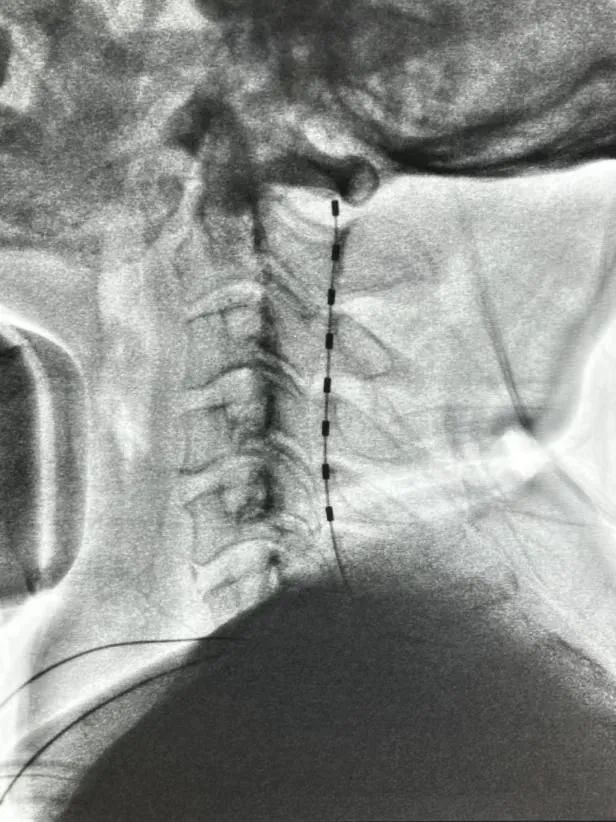

脊髓电刺激(Spinal Cord Stimulation, SCS)是一种将电极植入患者颈部脊髓硬脊膜外,以一定的脉冲电流对脊髓神经进行持续电刺激的新技术。研究证实颈段脊髓电刺激能明显增加脑血流量,减轻脑水肿,增加糖代谢并显著阻止脑萎缩的进程,同时提高脑脊液中多巴胺、去甲肾上腺素水平,减少氧化应激,另外高颈段脊髓电刺激还能激活胆碱能上行网状系统,从而起到促醒的作用。